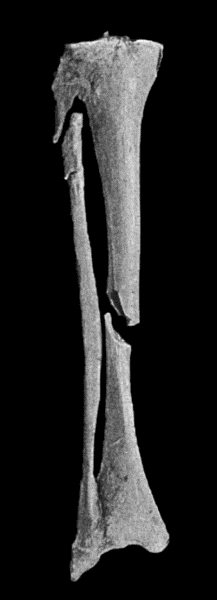

| 1. | Multiple Fracture of both Bones of Leg | 4 |

| 2. | Radiogram showing Comminuted Fracture of both Bones of Forearm | 5 |

| 3. | Oblique Fracture of Tibia; with partial Separation of Epiphysis of Upper End of Fibula; and Incomplete Fracture of Fibula in Upper Third | 6 |

| 4. | Excess of Callus after Compound Fracture of Bones of Forearm | 9 |

| 5. | Multiple Fractures of both Bones of Forearm showing Mal-union | 11 |